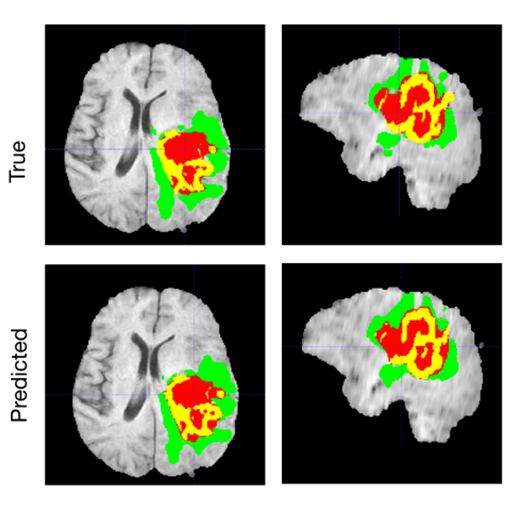

[4] Myronenko, Andriy, and Ali Hatamizadeh. “Robust Semantic Segmentation of Brain Tumor Regions from 3D MRIs.” In Brainlesion: Glioma, Multiple Sclerosis, Stroke and Traumatic Brain Injuries: 5th International Workshop, 2019.